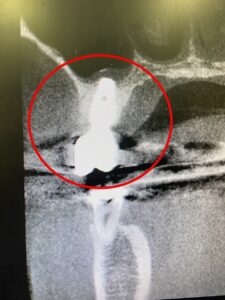

こちらはCTレントゲンの写真です。